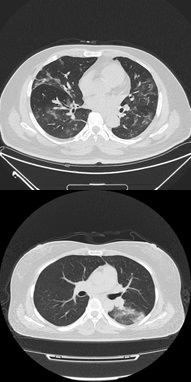

Figure 2: CT scan images showing ground-glass opacities in con-firmed COVID-19 positive patient.

Deep learning is a subset of machine learning involved with algorithms stimulated by the shape and role of the brain called artificial neural networks (ANNs). In simple words, deep learning can be thought of as a way to computerize advanced analytics that uses both new and historical data to predict activity. Similar to how humans learn from knowledge and experience gained over time, the deep learning model would perform a task many times, each time adjusting it a little to enhance the output. Deep learning is a significant component of data science, which includes advanced analytics [14, 15] and predictive modeling [16, 17, 18]. Various techniques are used to create strong deep learning models, including learning rate decay, training from scratch, transfer learning, and dropout. To date, deep learning is rising as the foremost machine-learning tool in the general imaging and computer vision domains [13]. CNNs have been demonstrated and tested to be powerful tools for a vast extent of computer vision tasks. Studies indicate that medical image analysis groups are quickly adapting to the field of CNNs and other deep learning techniques to a wide variety of applications [13]. In medical diagnostics, the assessment of disease relies on both image interpretation and image acquisition. With evolving technology, image attainment has improved substantially over recent years, with improved devices to capture increased-resolution images. However, image interpretation has recently begun to benefit from computer vision technology. Most of the medical image interpretations are performed by physicians. These human-intervened interpretations are limited to subjectivity, with large variations across physicians. Deep learning has proven to be the state-of-the-art basis among many computerized tools, leading to enhanced precision [19]. Deep learning models use networks composed of many convoluted layers that transform the input data (i.e., images/text) to outputs (e.g., lesions present/absent or disease present/absent) [19]. Deep learning techniques can be used for the early detection of COVID-19 patterns from CT scans of patients. Furthermore, besides the etiological lab confirmation, another primary detection element that assists in identifying COVID-19 pneumonia involves chest tomography imaging and clinical features epidemic [7]. As COVID-19 belongs to the Coronaviridae family, it has similar imaging features to SARS-COV and MERS-COV [5]. As the pandemic progresses and new findings come up, many radiologists report a pattern in the CT scans of patients with COVID-19. The typical features of the CT scan pattern include bilateral, multi-modal, and peripheral ground-glass opacities in the lungs, minor lung lesions, consolidations, ill-defined margins, and light pre-dominance in the light lower lobe of the lungs [20, 1]. The CT findings can be seen in asymptomatic patients, and the lesions are evolved into glass opacities and consolidation patterns on the onset of disease [21]. The ground-glass opacity was seen in 86% of infected patients, and it involved 76% bilateral region of the lung in the initial chest CT scans [5]. Figure 2 shows the CT scan images showing ground-glass opacities in confirmed COVID-19 positive patients. Ning et al. [7] proposed a deep learning model using clinical features along with CT scan images. They created open-source clinical data of patients with COVID pneumonia in two cohorts comprising patients with confirmed COVID-19 pneumonia, negative COVID-19 patients, and suspected individuals, and all their CT scan images, clinical features, and lab test results were retrieved. Cohort 1 had data from patients with community-acquired pneumonia, healthy individuals, and negative tested patients for COVID-19. Cohort 2 was used as validation data set with confirmed COVID-19 patients and control cases. The data from cohort 1 and cohort 2 was further divided into type 1 (morbidity outcomes) and type 2 (mortality outcomes) patients. Further, they developed a framework of hybrid learning (HUST-19) using cohort 1 data to diagnose confirmed and suspected cases with mild, regular, severe, and critically ill groups. Their hybrid model is comprised of four steps: in step one, they classified individual CT slices into positive CT images, non-informative CT images, and negative CT images using VGG-16 deep learning architecture (six convolutions and two dense layers) with an area under curve (AUC) value of 0.994. In step two, 13 layers of CNN were utilized to change the CT sliced-based prediction to individual patient-based prediction. Using seven deep neural networks, clinical feature-based prediction of patients was implemented, which got an AUC value of 0.978, 0.921, and 0.931 for type 1 and type 2 patients. In the final step, the authors integrated the CT-based and clinical feature-based slices to predict morbidity and mortality results of patients using penalized logistic regression. In addition to the implemented hybrid algorithm by Ning et al. [7], they implemented the Inception-Net-V3 model and Chex Net model using cohort 1 data. The outcomes show that all the models used have similar accuracy in predicting the morbidity and mortality results. Another work by Sharma et al. [22] classifies CT scans between COVID-19 pneumonia and other viral pneumonia using machine learning [22]. The system is built on the residual neural network architecture of Microsoft Azure. The model contained 800 CT images of COVID-19 infected patients, 800 CT images of healthy people, and 600 CT images of other viral pneumonia, which gave overall accuracy of almost 91% with some false indications. This article also discusses whether the Chest CT scan can be the alternative test for the current RT-PCR screening test. Liu et al. [23] proposed a machine learning framework to differentiate COVID-19 pneumonia from general pneumonia. Prior to the feature extraction being performed, their framework implemented a region of interest (ROI) delineation founded on the glass opacities on 73 confirmed COVID patients and 27 general cases of pneumonia. The relief algorithm was used to select features from the 34 extracted features. The authors classified the features using the ensemble of the bagged tree (EBT) algorithm along with logistic regression, SVM, decision tree, and KNN with Minkowski distance [23]. Their method yielded 88.6% sensitivity, with EBT giving all the classifiers consistent performance. They stated that the study could be improvised with more amount of data. Another study by Lin Li et al. [24] developed a 3D deep learning model referred to as COV-NET for diagnosing COVID-19 using volumetric chest CT. The study in [24] included CT scans of community-acquired pneumonia and other non-pneumonia abnormalities. The deep learning model was developed on ResNet architecture and gained a sensitivity of 90%. Initially, the region of interest is obtained by using U-net [25]. The model first extracts features combined through max-pooling operations before feeding into the SoftMax activation function [26] to generate a probability score for classifying each type (COVID-19, Community-acquired pneumonia, and non-pneumonia). Multinational data was collected, and multiple classifications were performed to increase the generalizability of detecting COVID-19 using CT scan images [8]. The authors developed hybrid 3D and full 3D models based on Densenet-121 architecture, giving them up to 90.8% accuracy. Initially, the lung segmentation model was developed using AH-Net architecture, followed by image classification models. Only a 10% false-positive rate was noticed in 140 patients with confirmed COVID pneumonia and other pneumonia.